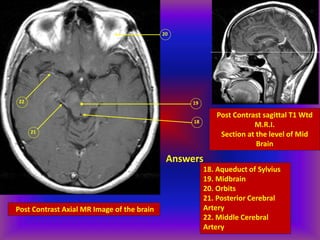

Post Contrast Axial MR Image of the brain

Post Contrast sagittal T1 Wtd

M.R.I.

Section at the level of Mid

Brain

Answers

18. Aqueduct of Sylvius

19. Midbrain

20. Orbits

21. Posterior Cerebral

Artery

22. Middle Cerebral